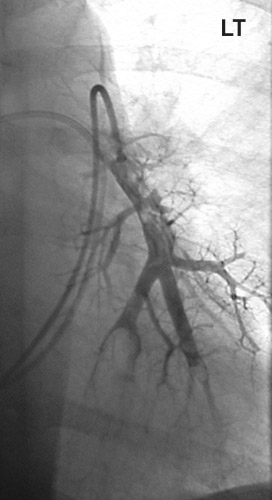

Image 2.2

This a thoracic CT angiogram that demonstrates lack of contrast extending to pulmonary arterial branches on the left